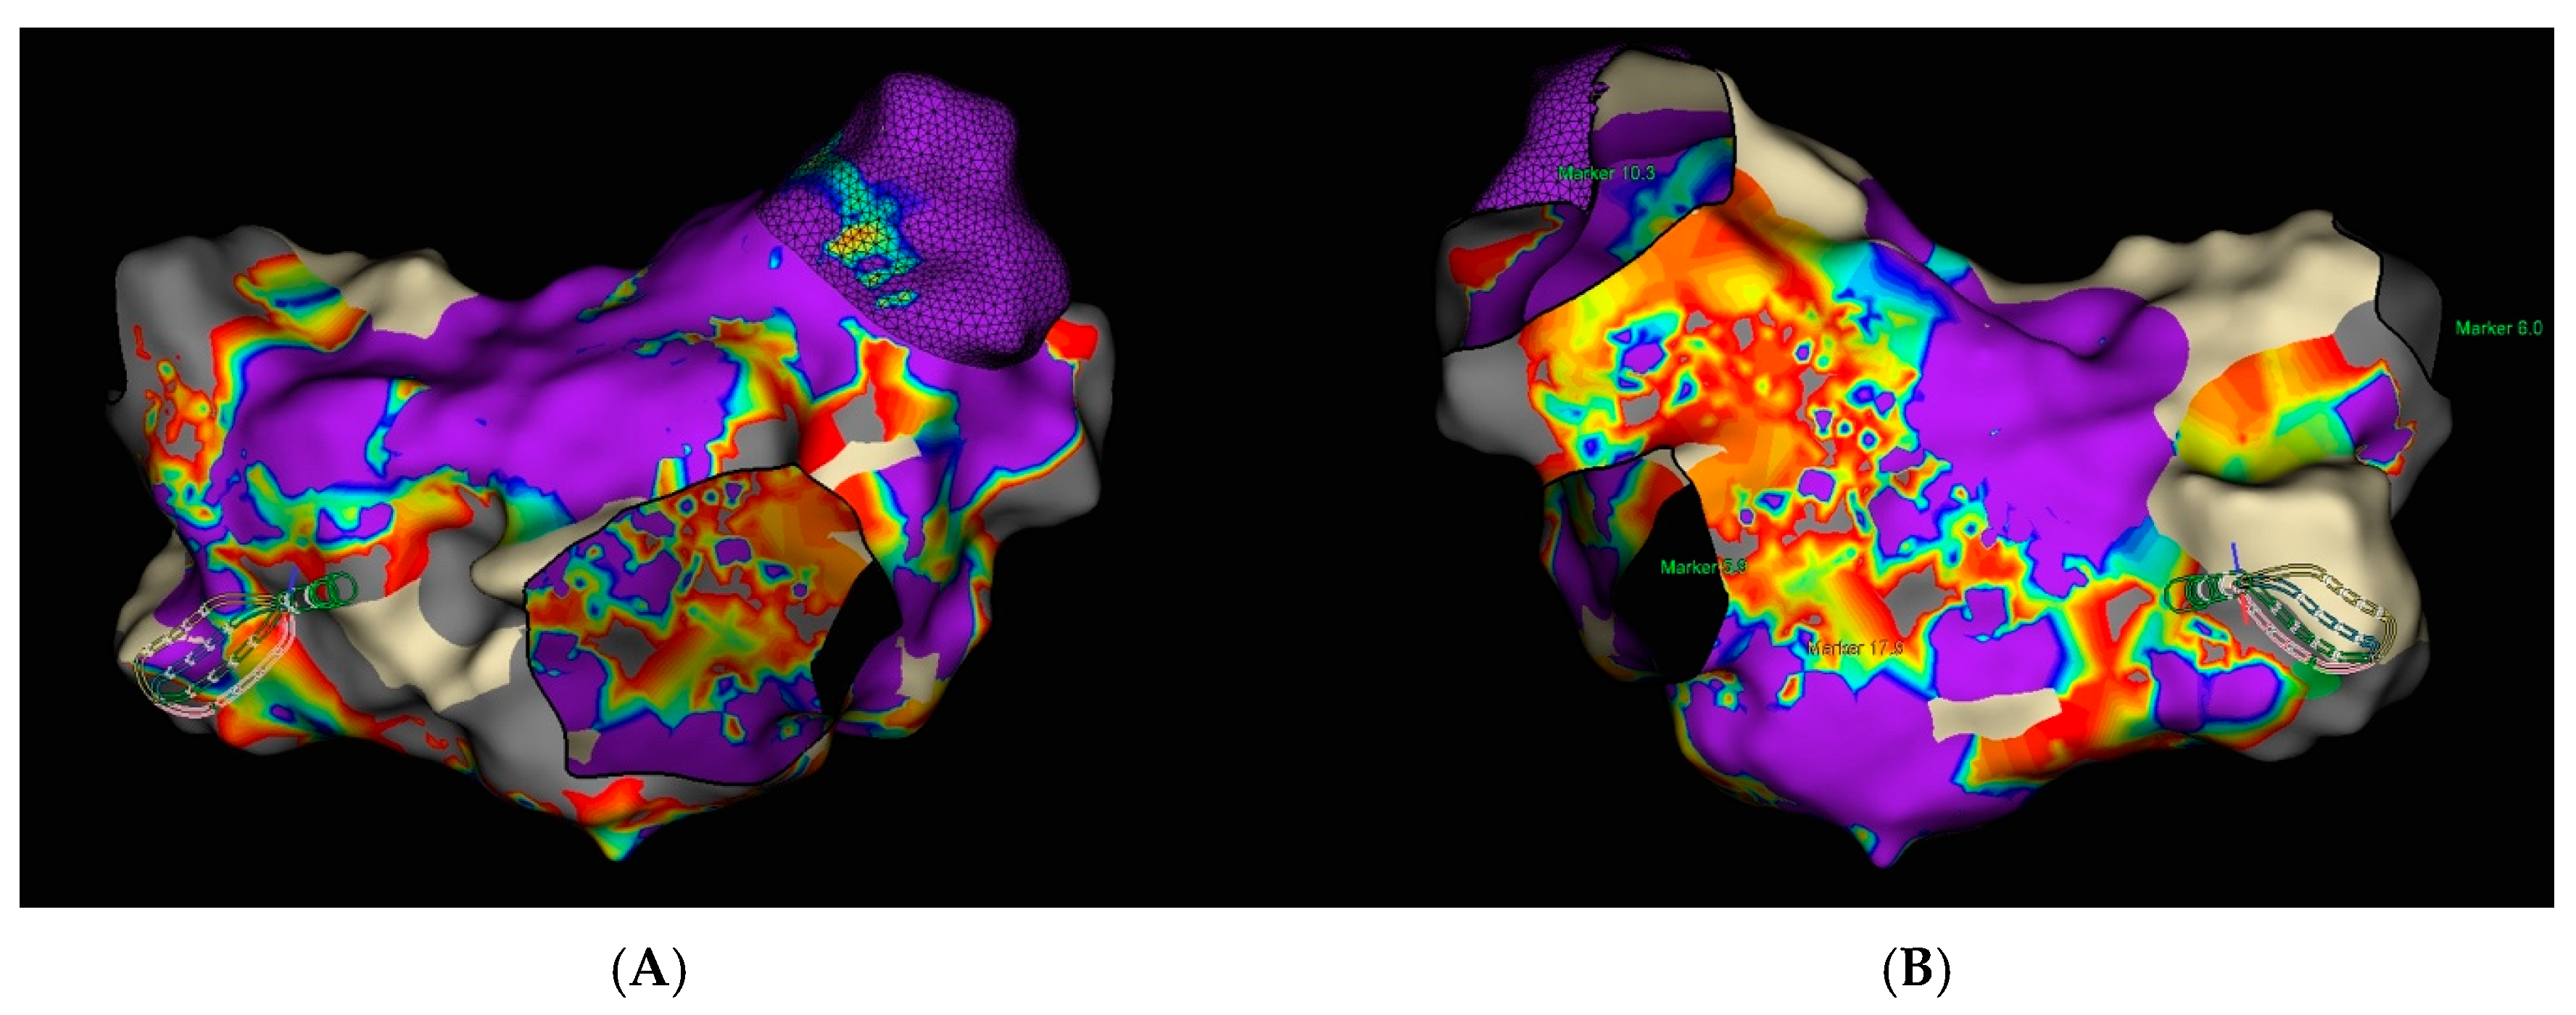

Transesophageal echocardiography (TEE) was performed to exclude the presence of intracardiac thrombi in the left atrium and left atrial appendage. Under local anesthesia, a diagnostic electrode was introduced via the right femoral vein into the coronary sinus (CS) and to the His bundle region in the right ventricle. A single transseptal puncture was performed, and a diagnostic Advisor HD Grid catheter was advanced into the left atrium through a steerable Agilis sheath. An electroanatomic map of the left atrium was created during ongoing AF (Figure 5).

Figure 5. Electroanatomic map of the left atrium during atrial fibrillation created using the Ensite X system (Advisor HD Grid mapping): (A) Posterior–Anterior view; (B) Anterior–Posterior view.